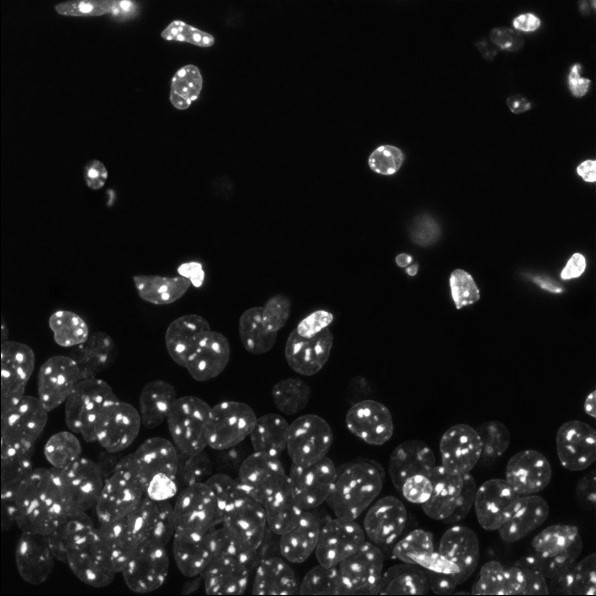

Epilepsy Research Institute UK have run a feature on Dr Amol Bhandare, co-lead for their Mortality, Morbidity & Risk research theme. Find out about our hopes for the research theme, as well as our research investigating the role of non-neuronal brain cells called ‘glia’ in epilepsy.